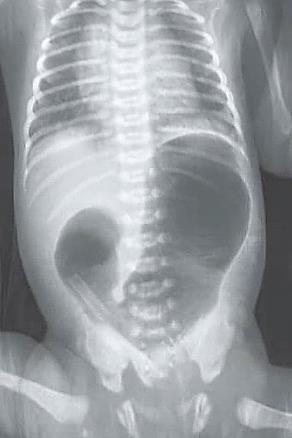

Recém-nascido de 37 semanas, parto cesárea e presença de polidrâmnio durante a gestação, com 8 horas de vida iniciou com vômitos biliosos após as primeiras mamadas e não eliminou mecônio. Ao exame físico, nota-se distensão abdominal discreta em epigástrio. Foi realizada radiografia de abdome (foto a seguir):

Fonte: Tratado de pediatria, 6ed, 2024.

De acordo com o quadro clínico e a imagem do exame, assinale a alternativa que apresenta a principal hipótese diagnóstica.